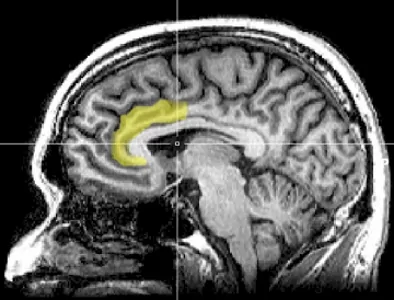

هیپنوتیزم باعث تغییراتی در فعالیت و اتصال مغز میشود که با کاهش خودآگاهی، افزایش کنترل احساسات درونی و نگرانی کمتر سازگار است. مطالعهای که توسط محققان دانشگاه استنفورد در ژوئیه 2016 انجام شد، آنچه را که در طول هیپنوتیزم در مغز اتفاق میافتد، بررسی کرد. تصویربرداری رزونانس مغناطیسی کاربردی (fMRI) برای مشاهده فعالیت مغز در 57 نفر در هیپنوتیزم استفاده شد. تغییرات در سه ناحیه خاص مغز مشاهده شد و نشان داد که:

- کاهش اتصال بین قشر پیشپیشانی - پشتی جانبی (بخشی از شبکه کنترل اجرایی درگیر در برنامه ریزی و تصمیم گیری) و قشر کمربندی خلفی (بخشی از شبکه حالت پیش فرض فعال در طول تفکر مرتبط با خود). این ارتباط کاهشیافته بین برنامهریزی اقدامات و خودآگاهی ممکن است دلیل فوری بودن عملی باشد که در طول هیپنوتیزم انجام میشود. در هیپنوتیزم، مانند حالتهای جذب عمیق در یک کار یا عملکرد، شخص به طور خود به خودی عمل میکند، بدون اینکه در مورد اعمال فکر کند.

- افزایش اتصال بین قشر جلویی پیشانی - پشتی جانبی (بخشی از شبکه کنترل اجرایی درگیر در برنامه ریزی و تصمیمگیری) و اینسولا (بخشی از شبکه برجسته که در حس کردن و تنظیم فرآیندهای درونی بدن نقش دارد) این ممکن است مسئول افزایش کنترل بر فرآیندهای بدنی و عاطفی در هیپنوتیزم باشد.

- کاهش فعالیت در قشر کمربندی قدامی پشتی (بخشی از شبکه برجسته که در ارزیابی احساسی خطاها و نگرانیها نقش دارد). ACC پشتی نیز در حین عملکرد پر تلاش فعال است. این کاهش فعالیت ممکن است توضیح دهد که چرا در هیپنوتیزم و حالتهای جذب عمیق، اعمال و عملکرد بدون زحمت و با نگرانی کمتر انجام میشود.

DMN شبکهای از نواحی مغزی متقابل است و زمانی فعال است که فرد درگیر کاری نیست و در هنگام فکر کردن، به خاطر سپردن و رویاپردازی است. DMN زمانی که فردی درگیر یک کار هدفمند باشد یا توجه او کاملاً جذب چیزی شده باشد فعال نیست. هیپنوتیزم فعالیت DMN را کاهش میدهد. کاهش فعال شدن DMN در تمرین کنندگان طولانی مدت مدیتیشن نیز مشاهده میشود. این واقعیت که مغز تحت هیبنوتیزم کاهش فعالیت DMN را نشان میدهد، از تعریف هیپنوتیزم به عنوان یک حالت جذب توجه پشتیبانی میکند، نه حالتی که در آن فرد هوشیاری خود را از دست میدهد. هیپنوتیزم پاسخهای عصبی مشابه تفکر مفهومی خود به خودی را نشان میدهد. شاید به همین دلیل است که هیپنوتیزم میتواند خلاقیت و بینش را برانگیزد.

نواحی جلویی مغز در توانایی فرد برای تمرکز، که به عنوان کنترل توجه شناخته میشود، نقش دارند. کنترل توجه ارتباط تنگاتنگی با کارکردهای اجرایی مانند استدلال، حل مسئله، برنامهریزی، خودکنترلی و انعطاف پذیری شناختی (توانایی تفکر همزمان درباره چندین مفهوم) دارد. هیپنوتیزم فعالیت سیستمهای درگیر در این عملکردها را افزایش میدهد و در اعتیاد و ADHD دچار اختلال میشوند.